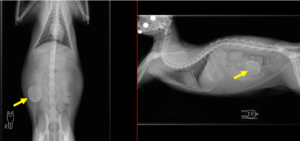

―レントゲン検査:右の下腹部に透過性の低い構造物を確認。

―エコー検査:液体を含む嚢胞状(のうほうじょう)の構造物を確認 。